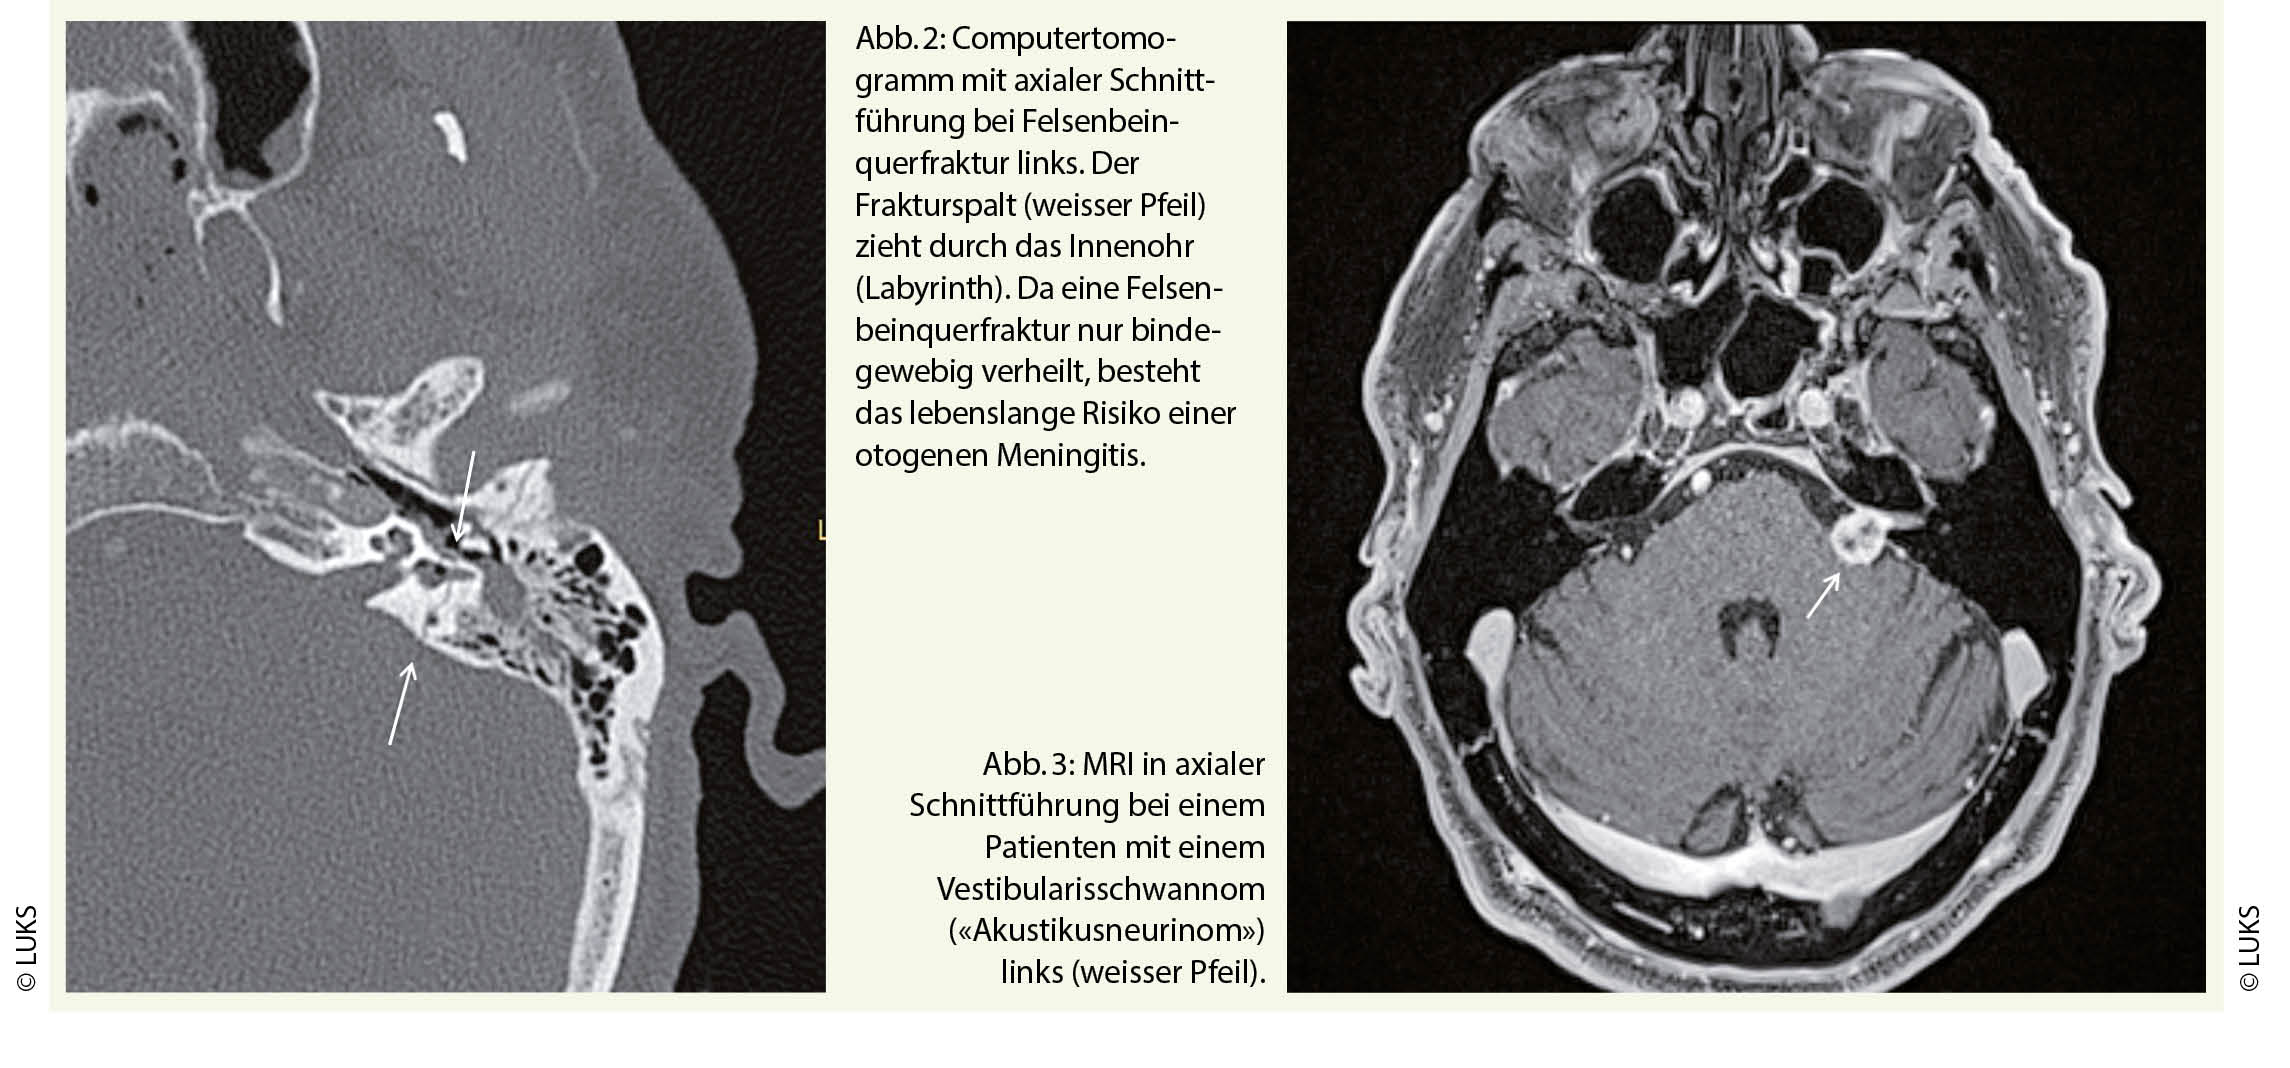

Neben dem akuten hochgradigen Hörsturz stellt die Felsenbeinquerfraktur den zweithäufigsten Grund für eine Ertaubung im Erwachsenenalter dar. Bei den Felsenbeinfrakturen können eine Querfraktur von einer Längsfraktur bereits klinisch mittels Stimmgabelprüfungen unterschieden werden. Bei der Felsenbeinlängsfraktur resultiert eine Schallleitungsschwerhörigkeit, entsprechend wird im Versuch nach Weber die Stimmgabel ins betroffene Ohr lateralisiert. Dem gegenüber tritt bei der Felsenbeinquerfraktur eine Ertaubung auf, sodass die Stimmgabel ins hörende Gegenohr lateralisiert wird. Die Felsenbeinquerfraktur zieht durch das Innenohr, also durch die Cochlea und das Labyrinth (Abb. 2).

Es tritt ein cochleo-vestibulärer Funktionsausfall mit einer Ertaubung und einem Vestibularisausfall auf. Neben der Ertaubung weist der Patient wegen des Vestibularisausfalls einen Spontannystagmus zum unverletzten Gegenohr auf, also einen Ausfallsnystagmus. Während der Schwindel durch die zentrale Kompensation des Vestibularisausfalls allmählich abklingt, persistiert die Ertaubung des betroffenen Innenohres. Zudem besteht lebenslang das Risiko einer otogenen Meningitis, da im Bereich der otischen Kapsel eine Fraktur nur bindegewebig verheilen kann.

Eine Felsenbeinfraktur wird in der Computertomographie bestätigt. Da bei einer Felsenbeinquerfraktur die Ursache für eine Ertaubung offensichtlich ist, benötigt es keine weiteren Abklärungen. Demgegenüber muss bei einer Ertaubung nach einem Hörsturz im Verlauf eine intra- oder retrocochleäre Pathologie wie ein Vestibularisschwannom («Akustikusneurinom») ausgeschlossen werden (Abb. 3)